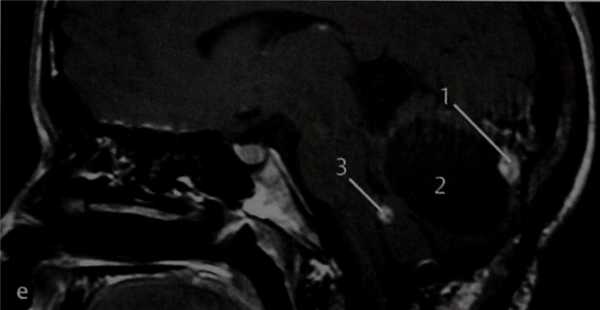

МРТ: Т1-взвешенное изображение в сагиттальной проекции после введения препарата гадолиния. При болезни Гиппеля-Линдау могут возникать и другие опухоли, что значительно усугубляет состояние пациентов, учитывая возможность сдавления этими опухолями жизненно важных анатомических структур и развития вторичной гидроцефалии. В данном случае развилась гемангиобластома с усиливающимся солидным (7) и неусили-вающимся крупным кистозным (2) компонентами. Опухоль значительно сдавливает мозжечок. Несколько кпереди визуализируются мелкие вторичные усиленные опухоли (3).